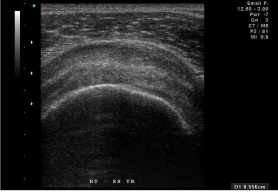

72.

85歲女性患者,主訴左肩疼痛超過6個月,有局部壓痛,無肌肉萎縮現象,圖為左肩部超音波檢查,上圖為旋轉環帶長軸切 面,下圖為短軸切面,最可能之診斷為何? (A)風濕性關節炎(rheumatoid arthritis) (B)棘上肌腱斷裂(supraspinatus tendon tear) (C)化膿性關節炎(pyogenic arthritis) (D)肩三角肌撕裂(deltoid muscle tear)